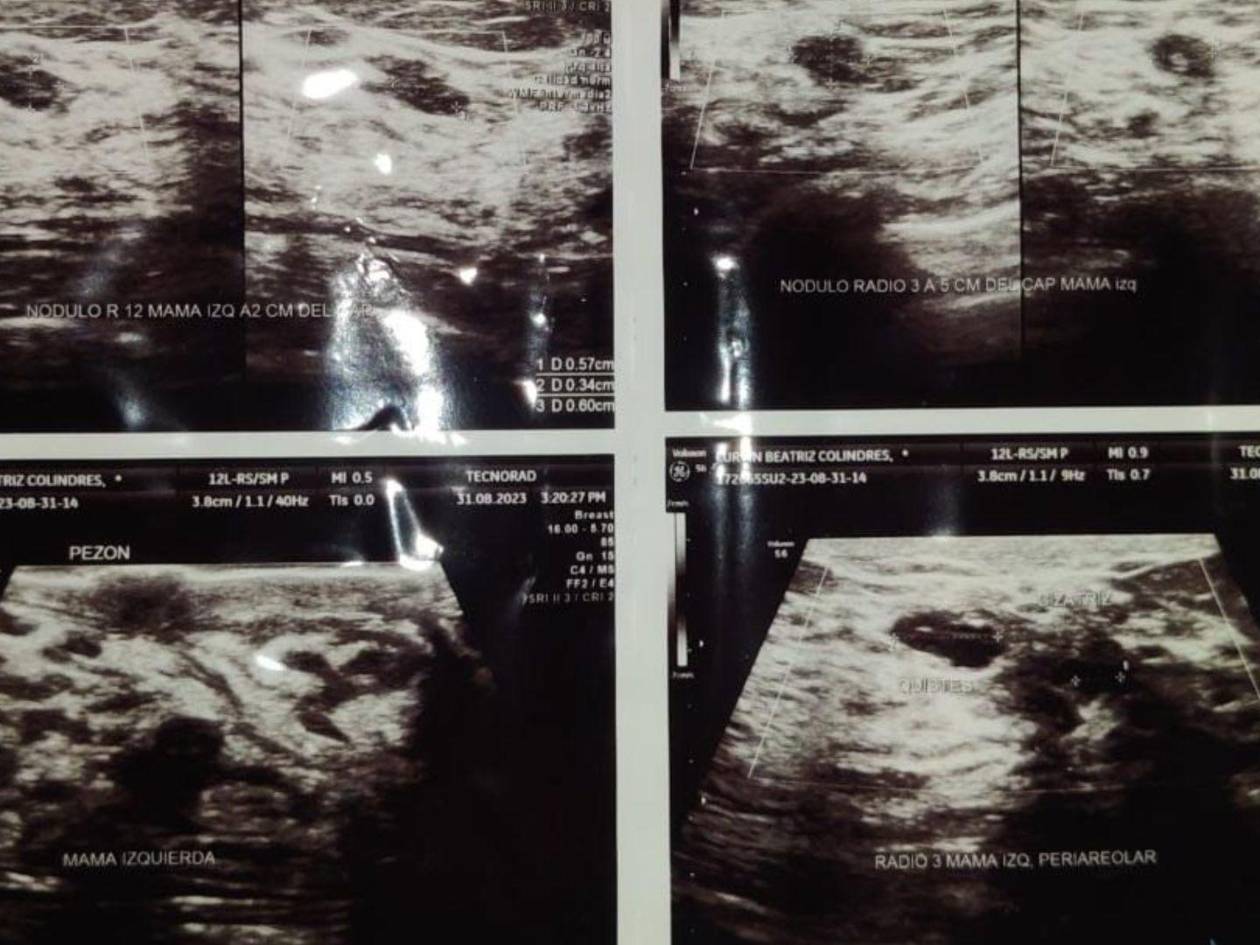

Lurvin Colíndres, estudiente de Derecho en San Pedro Sula, esperó cirugía tras ser diagnosticada con nódulo BI-RADS 4 y tuvo que operarse en el sector privado para evitar que evolucionara a cáncer

A finales de 2018 recibió la noticia que tenía un nódulo en la mama izquierda BI-RADS 4, una clasificación que no es cáncer aún, pero que exige vigilancia inmediata, porque una vez llegase a categoría 6 ya no había vuelta atrás.

Según el Colegio Americano de Radiología, la clasificación BI-RADS 4 implica una lesión sospechosa de malignidad, con una probabilidad de cáncer que puede oscilar entre el 2% y el 95%, dependiendo de la subcategoría. No es cáncer confirmado, pero tampoco es una simple irregularidad, exige biopsia y seguimiento inmediato.

Ultrasonido que mostraba los resultados preliminares de la condición de una de las mamas de Lurvin Colindres.